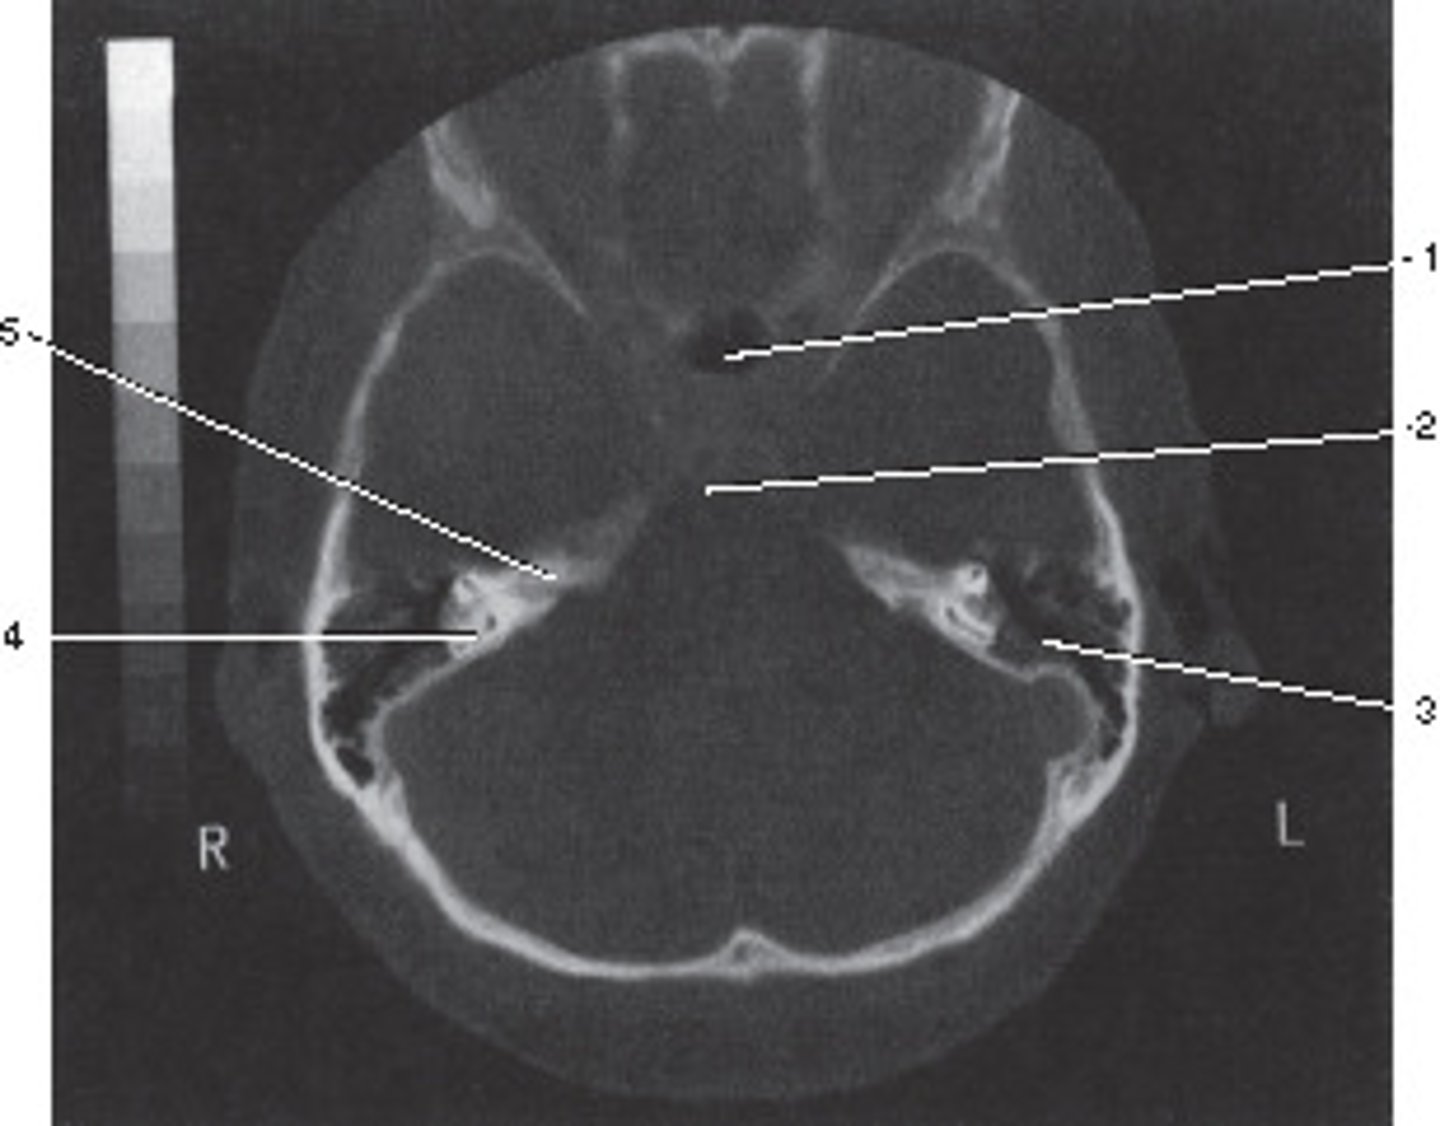

Number 2 corresponds to which of the following?

<p>Number 2 corresponds to which of the following?</p>

Number 5 corresponds to which of the following?

<p>Number 5 corresponds to which of the following?</p>

Number 3 corresponds to which of the following?

<p>Number 3 corresponds to which of the following?</p>

Which number corresponds to the vestibule?

<p>Which number corresponds to the vestibule?</p>